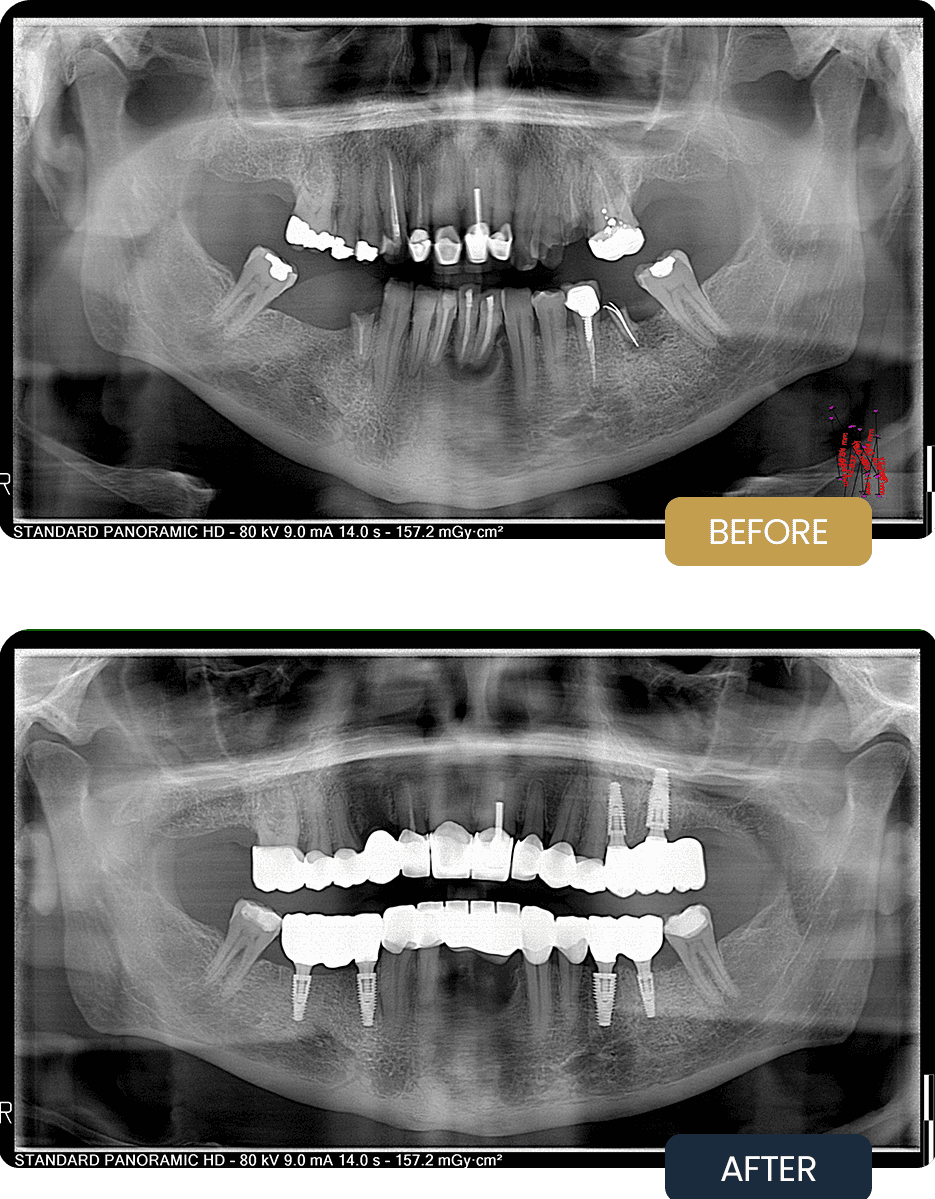

BEFORE

Craig presented with missing teeth and failing restorations, resulting in reduced chewing efficiency and compromised long term dental stability.

Clinical examination and panoramic imaging showed areas where implant support was required to restore function and provide a stable foundation for fixed crowns.

AFTER

Post treatment panoramic imaging confirmed stable implant placement and well integrated restorations.

The final result provided Craig with a fixed, functional bite and improved long term dental stability, allowing him to eat comfortably and maintain oral health with confidence.